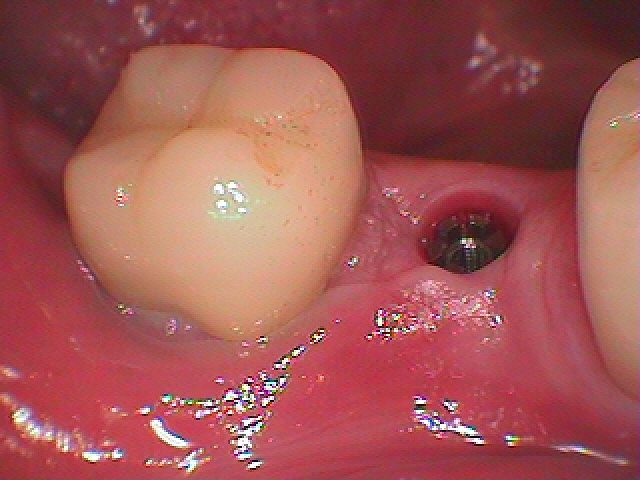

上部構造が入った時のものです。 ケア次第では20年30年と持ってもらえることをねがいます。| |広島市安佐南区の歯科医院 上部構造が入った時のものです。 ケア次第では20年30年と持ってもらえることをねがいます。 トップ お知らせ・ブログ 上部構造が入った時のものです。 ケア次第では20年30年と持ってもらえることをねがいます。 上部構造が入った時のものです。 ケア次第では20年30年と持ってもらえることをねがいます。 Web診療予約 初めての方へ 選ばれ続ける理由 院内設備について 歯が痛いしみる一般歯科 歯がぐらぐらする歯周病 健康な歯を保ちたい予防歯科 子供の虫歯予防をしたい小児歯科 銀歯をセラミックに審美歯科 白い歯を目指しませんか?ホワイトニング 矯正専門医がいるので安心矯正歯科 抜けた歯を補いたいインプラント・入れ歯 医院案内 スタッフ紹介 メリィハウス歯科クリニックオフィシャルホームページ ラベンダー歯科クリニックオフィシャルホームページ お知らせ・ブログ ホーム 診療科目 一般歯科 歯周病治療 予防治療 小児歯科 審美治療 ホワイトニング 矯正歯科 入れ歯・インプラント マウスピース矯正 初めての方へ 院長・スタッフ 設備紹介 医院案内・アクセス メニューを閉じる